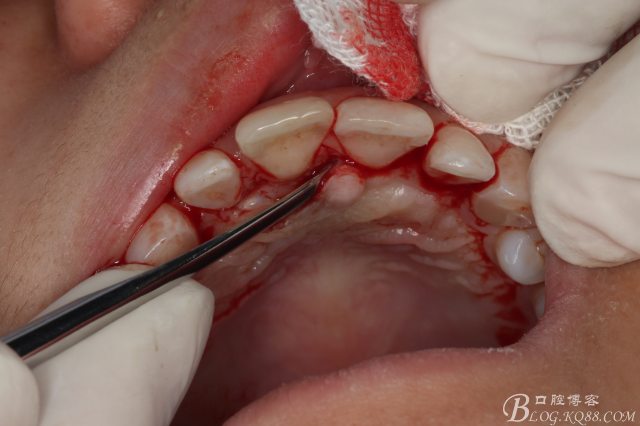

圖8.翻瓣暴露出鼻腭神經(jīng)管及腭側(cè)骨面

圖9.在切牙管旁邊去骨、暴露出21根尖區(qū)多生牙牙根

圖10.繼續(xù)去骨、發(fā)現(xiàn)多生牙部分位于鼻腭管內(nèi)